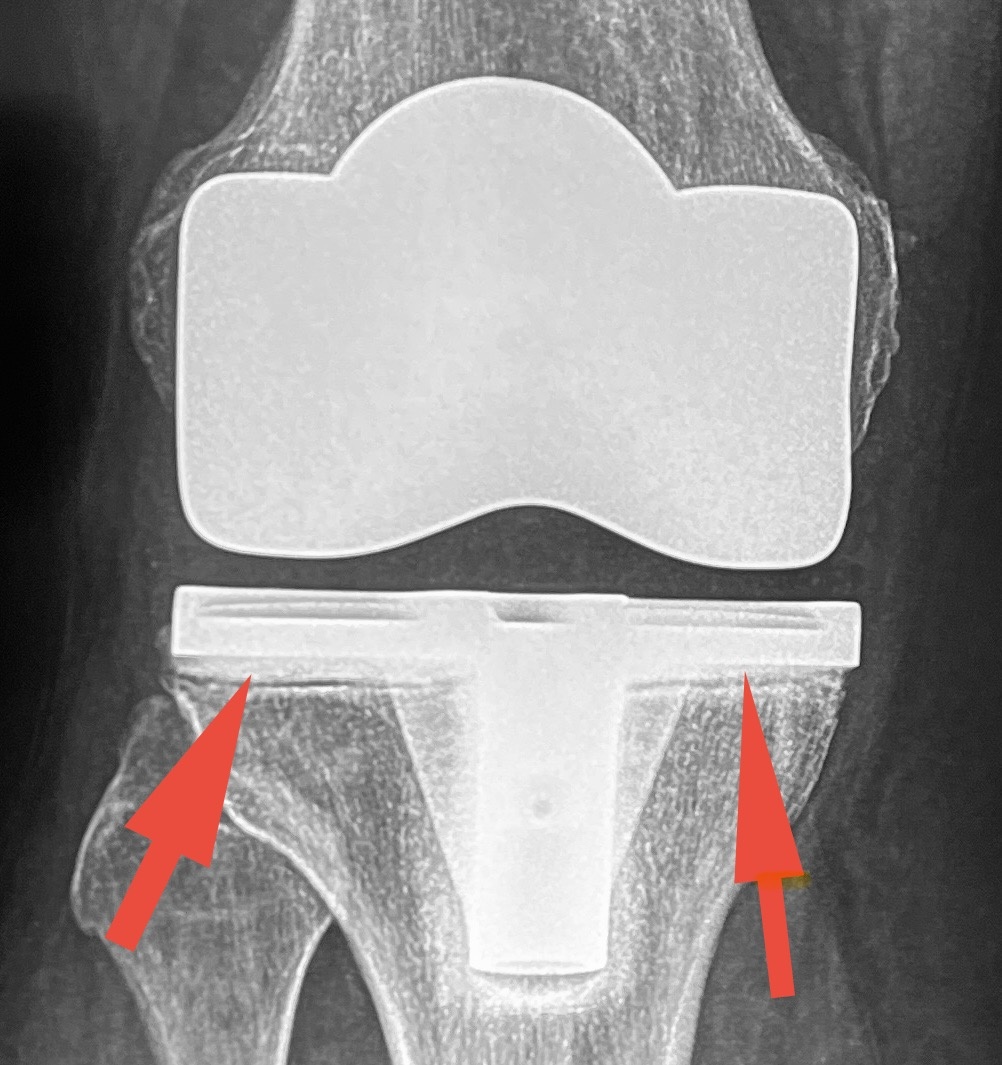

Женщина хорошо за 60. В Германии 10 лет назад сделала одномыщелковое протезирование коленных суставов (писал о таком недавно). Через год из-за расшатывания одного протеза заменили его на тотальный. Еще через пару лет и второй заменили на тотальный. В обоих случаях инфекции не было - асептическое расшатывание. Сразу после последней операции в колене нестабильность, ощущение неустойчивости. Как-то приспособилась, ходила, ограничивала себя, но терпела. Наконец, терпение кончилось. Пошла у нас по врачам, и тут мнения разделились. Одни считали, что есть нестабильность сустава (то есть, связки не работают), другие - что проблема в нестабильности самого эндопротеза.

Я считал, что оба фактора имеют право быть. То есть, двигаются и части искусственного сустава:

Стрелки указывают на линии, характерные для нестабильности

и связочный аппарат не работает. Кстати, стоял сустав, при котором сохраняется задняя крестообразная связка - очень странный выбор.

На операции так и оказалось - связка оторвана, компоненты протеза подвижны, остальные связки не натянуты.

Вопросов - масса. Сам протез отличный, американский, в целом установлен хорошо. Но - нужна была немного другая конструкция, полиэтиленовый вкладыш должен был быть толще, и - вишенка на торте - весь костный цемент, которым протез приклеивается к костям, остался при удалении протеза на протезе!

Вот эта зернистая структура - цемент, который свободно отделился от костей. В норме мы его отбиваем долотами, он от протеза отделяется лучше. Здесь же налицо признак того, что протез не «прилип» к костям. Поэтому на рентгене и появились те самые линии. Щели между цементом и костью.